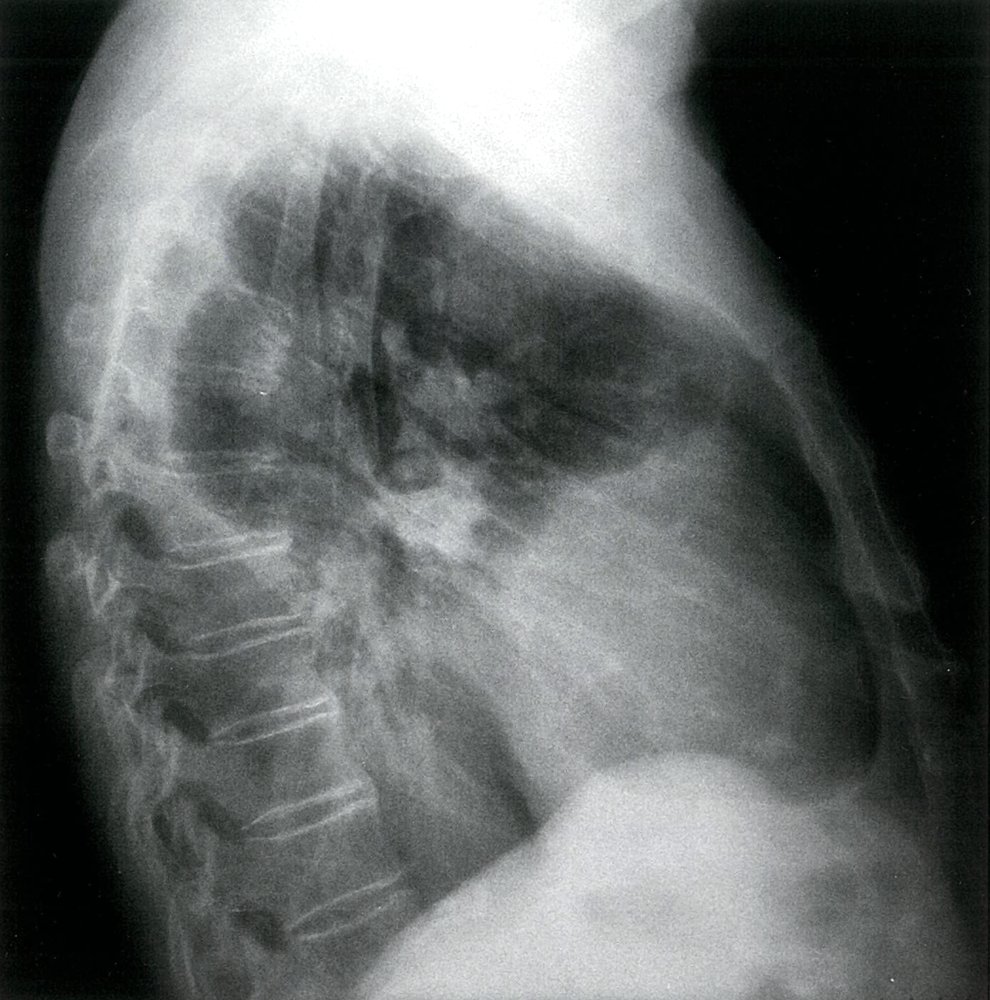

Chest x-ray is often performed as part of a routine workup for respiratory symptoms, however, HRCT has higher sensitivity and specificity (especially in early disease stages).

• Chest x-ray

• Signs of interstitialfibrosis (e.g., diffuse bilateral opacities, predominantly in the lower lobes)

• Pleural abnormalities (e.g., pleural plaques and pleural thickening) may be seen.

Although asbestos is commonly found in roofing materials, it predominantly affects the lower lobes of the lungs.